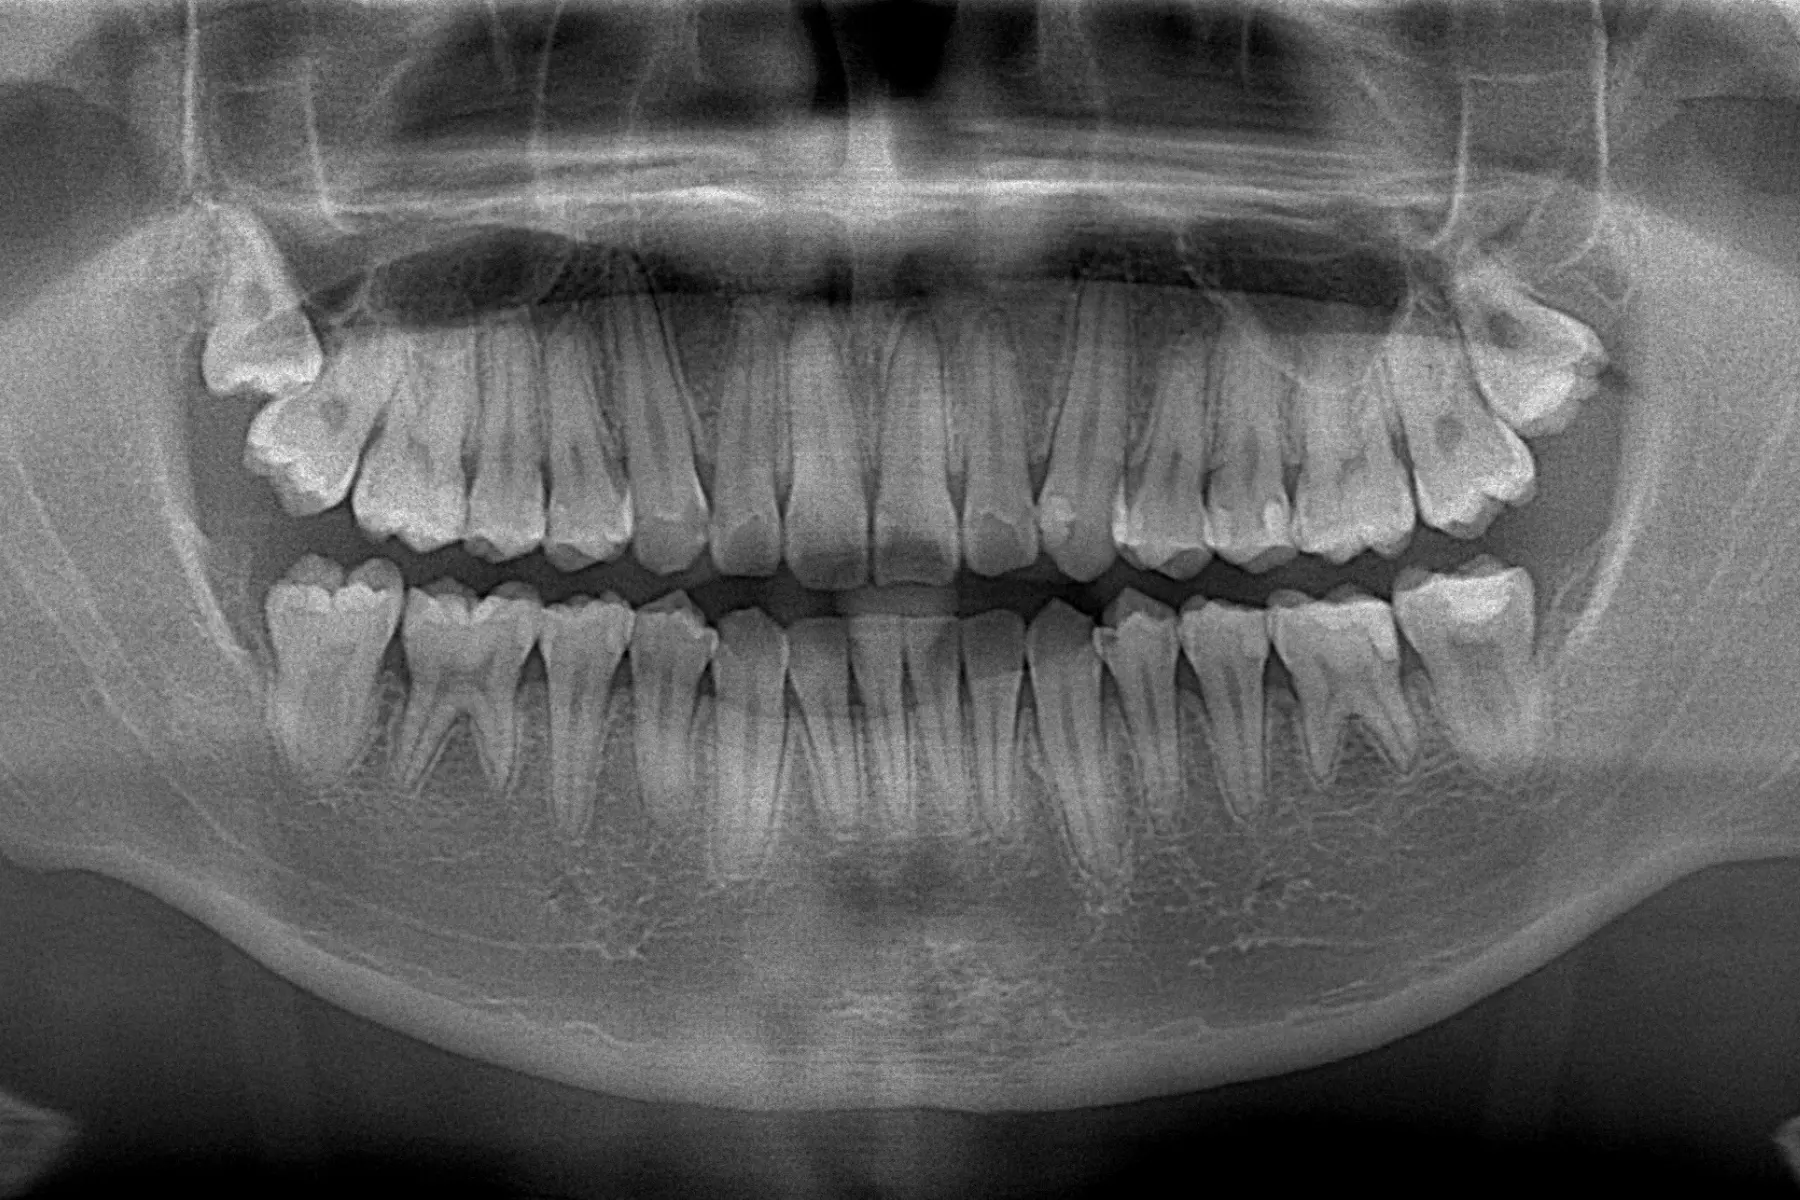

進行牙齒矯正,首先要先明白確定自己的困擾在哪裡,清楚瞭解自己的期望和需求是什麼,初次就診時,為了取得您全口的健康狀況,會先拍攝口內及口外數位照,環口 X 光片及側顱 X 光片,使用iTero element 5D 口掃,取得口腔內的3D模型,觀察目前的牙齒與口腔狀況並讓您了解目前的牙齒狀況,告訴您簡單的治療方向並會展示類似的案例及作法,讓您得知矯正後預見的變化,也會依據您的狀況為您量身打造適合的矯正療程方案!